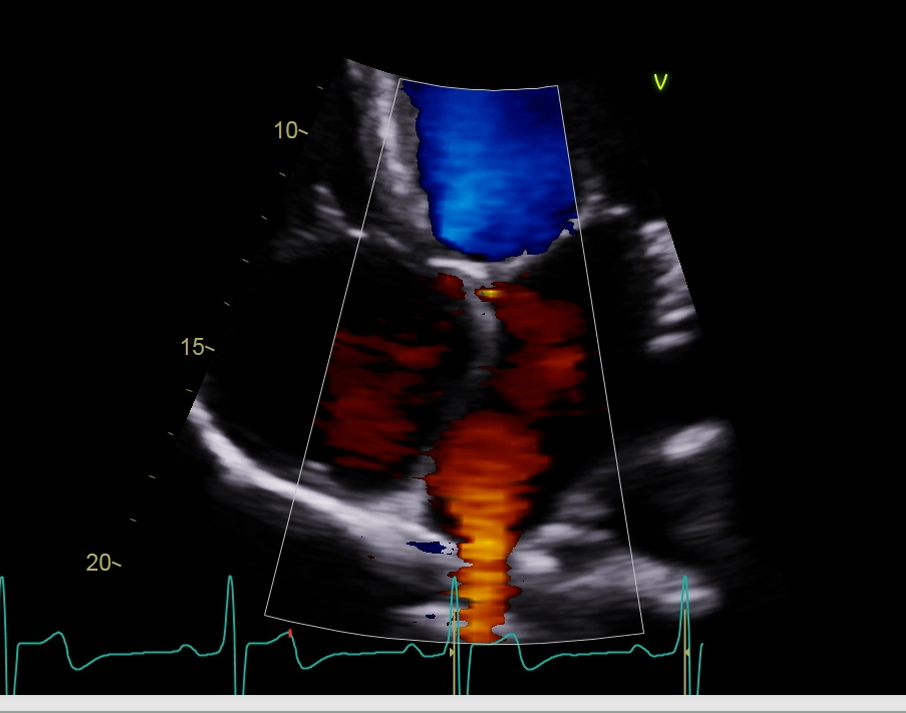

when we do our color flow what are we looing for the step we look at the pulmonary vein with color?

So, we look at the color of the pulmonary veins and for any MR, the normal flow pulmonary vein to LA to MV and the to LV, so any blue flow is going to be that MR reaching back and this red flow will be the pulmonary vein